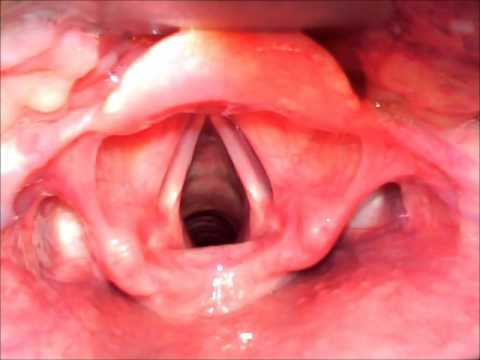

What are the 3 compartments of the larynx?

What tool can be used to view the vocal cords when intubating?

laryngoscope